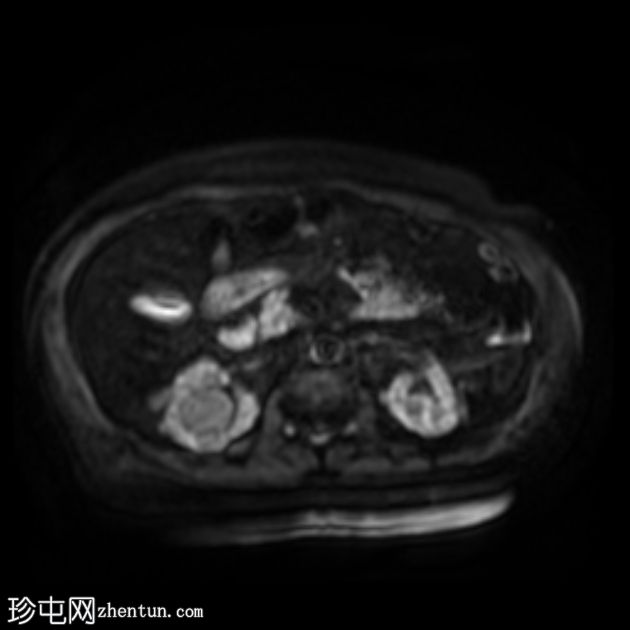

冠状位

T2加权像

双侧肾囊性疾病,可见多个肾囊肿,其中许多呈复杂性(出血性)囊肿,T1加权像呈高信号,T2加权像呈低信号。

左侧可见一较大的肾周血肿,与上极出血性囊肿相连,提示出血性囊肿破裂(Wunderlich综合征)。

未见肾脏软组织肿块。

轻度肝脾肿大,受检骨骼T2加权像呈弥漫性低信号,提示肾性骨营养不良。